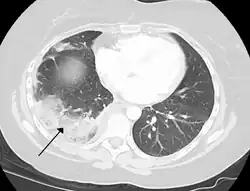

-

Chest CT (axial lung window) -

Chest CT (coronal lung window) -

Chest CT (axial lung window)

Chest CT (coronal lung window)